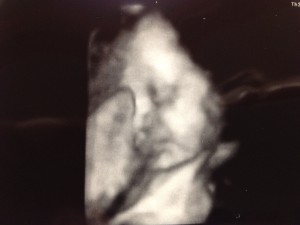

Baby Update- Well Mr. Man, we went to the Dr yesterday, and you are measuring 3lbs 10 oz. That puts you in the 43% percentile and the Dr said that was great and you are one day ahead of your due date. My placenta has moved up out of the way, so I don’t have to have a mandatory c-section. Yay! You were in the head down position and your feet were up by your head, so you were completely folded in half with your butt in my ribs! We got to see you wave your little finger around at us, and it was so cute! They also did a 3D pic of your face, and you definitely have fatter cheeks than the last time we got to see you! Since we are so close to the end (under 9 weeks!) I now start going to our appointments every 2 weeks so the Drs can keep an eye on everything. You’ve been having hiccups that make you really mad so you start squirming around all over the place. According to the baby books, you are about 16 inches long (they don’t actually measure you at the Dr’s office anymore because you are so big and squished up) and about the size of a pineapple. All 5 of your senses are in working order, although your nose won’t pick up anything until after you’re born since smell is transferred through air.

Here are the 3 ultrasound photos from the appointment including one of your boy parts! (Sorry, I know this will be soooo embarrassing when you’re older!)